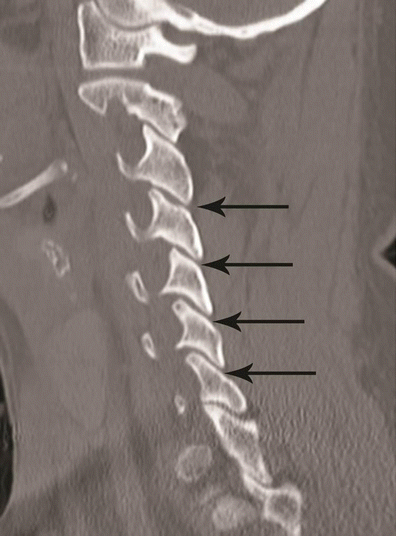

Hyperextension compression injury. a Parasagittal CT image shows C6, C7 articular pillar and process comminuted fracture with vertical orientation (black arrows). Focal anterior widening of C4–C5 facet joint (white arrow) is a characteristic feature of hyperextension injury. b Coronal CT image from the articular pillar in a different patient shows left C5 articular pillar fracture with vertical orientation and comminution (black arrow)